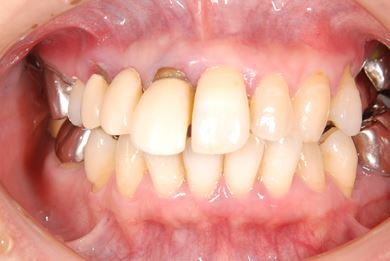

抜歯即日スピードインプラント治療+セラミック治療

| 性別/年齢 | 女性 / 49歳 | ||||||||||||||||||||||||||||||||

| 主訴 | 左奥歯のつめものが取れている所を治療したい。 | ||||||||||||||||||||||||||||||||

| 治療方針 | 抜歯と同時にインプラント埋入を行い、治療期間を短縮する。上前歯部、骨再生法によりインプラント治療を可能にする。 | ||||||||||||||||||||||||||||||||

| 治療内容 | インプラント4本(抜歯即日スピードインプラント、テンポラリーインプラント+仮歯)、メタルボンドセラミックブリッジ12本、メタルボンドセラミッククラウン3本(メタルボンド用土台1本) | ||||||||||||||||||||||||||||||||